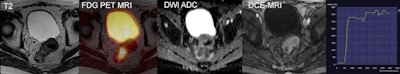

Figure 2: Combined F-18 FDG PET/MRI of a primary upper rectal cancer demonstrates a metabolically active tumor with restricted diffusion and type II enhancement curve. Images courtesy of King's College London.

Novel concepts toward intrinsic compensation of involuntary patient motion are being worked on, a prerequisite for subsequent partial volume correction (figure 1), or anatomic-guided image reconstruction. The better the alignment of the two sets of imaging information, the more valuable the clinical information of an integrated PET/MRI examination (figure 2). Also, the palette of PET/MRI scenarios is being expanded through the adoption of the concept of an automated image-derived input function as a prerequisite for parametric imaging, as well as through the adoption of novel radiotracers, such as gallium-68 prostate-specific membrane antigen (Ga-68 PSMA) for multiparametric PET/MR imaging of prostate cancer.